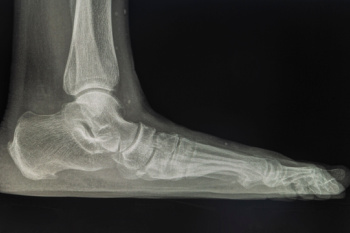

Heel spurs are bony growths that develop on the heel due to stress and inflammation in surrounding tissues. They are commonly seen in two forms. Heel spur syndrome affects the bottom of the heel, and insertional Achilles tendinitis affects the back of the heel where the tendon attaches. Risk factors include flat feet, high arches, excess weight, tight calf muscles, and repetitive impact activities. Symptoms may involve sharp heel pain, stiffness, and discomfort during the first steps of the day. A podiatrist can diagnose the condition, offer custom treatments, and provide guidance to relieve pain and improve function. If heel pain is limiting your daily life, it is suggested that you consult a podiatrist who can offer effective relief and treatment solutions.

Heel spurs are formed by calcium deposits on the back of the foot where the heel is. This can also be caused by small fragments of bone breaking off one section of the foot, attaching onto the back of the foot. Heel spurs can also be bone growth on the back of the foot and may grow in the direction of the arch of the foot.